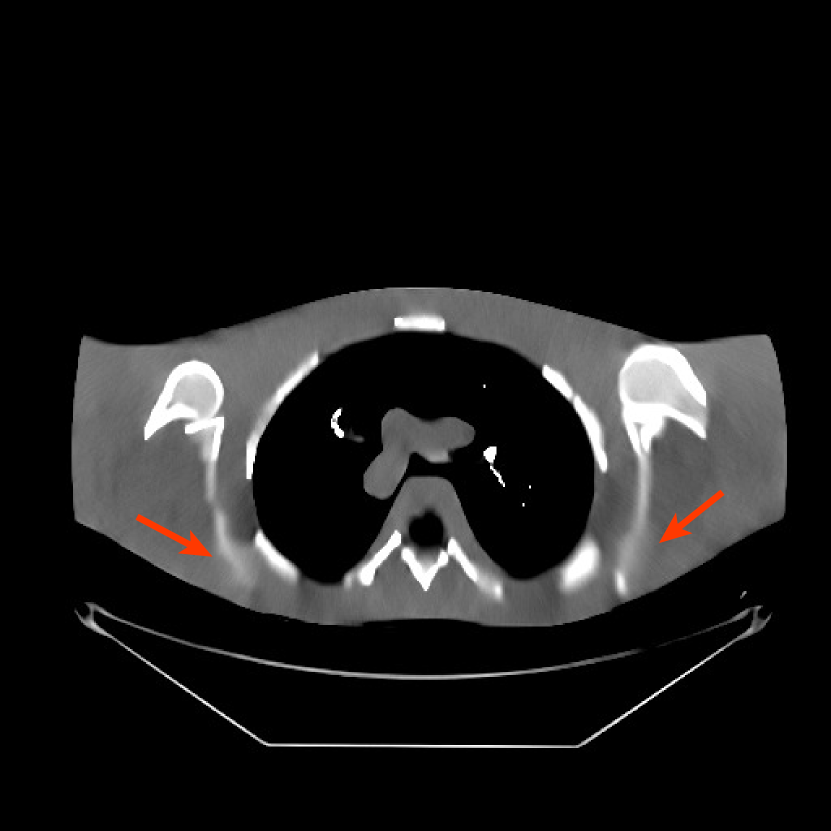

Fig. 9 shows three axial slices from the 3D reconstructions with SPULTRA and PWLS-ULTRA at : the middle slice (No. 67) and two slices located farther away from the center (No. 90 and No. 120). The image profiles along a horizontal line (shown in green) in the displayed slices are also shown in Fig. 9. The reconstructed slices using PWLS-ULTRA appear darker around the center compared to the “true” clinical image and the reconstructions with SPULTRA. This means PWLS-ULTRA produces a strong bias in the reconstruction. The bias can be observed more clearly in the profile plots: the pixel intensities for the SPULTRA reconstruction better follow those of the “true” clinical image, while those for the PWLS-ULTRA reconstruction are much worse than the “true” values. Moreover, SPULTRA achieves sharper rising and failing edges compared to PWLS-ULTRA. In other words, SPULTRA also achieves better resolution than PWLS-ULTRA. Fig. 9 also shows a zoomed-in ROI for each of the chosen slices, and highlights some small details with arrows. It is clear that in addition to reducing the bias, SPULTRA reconstructs image details better than PWLS-ULTRA.